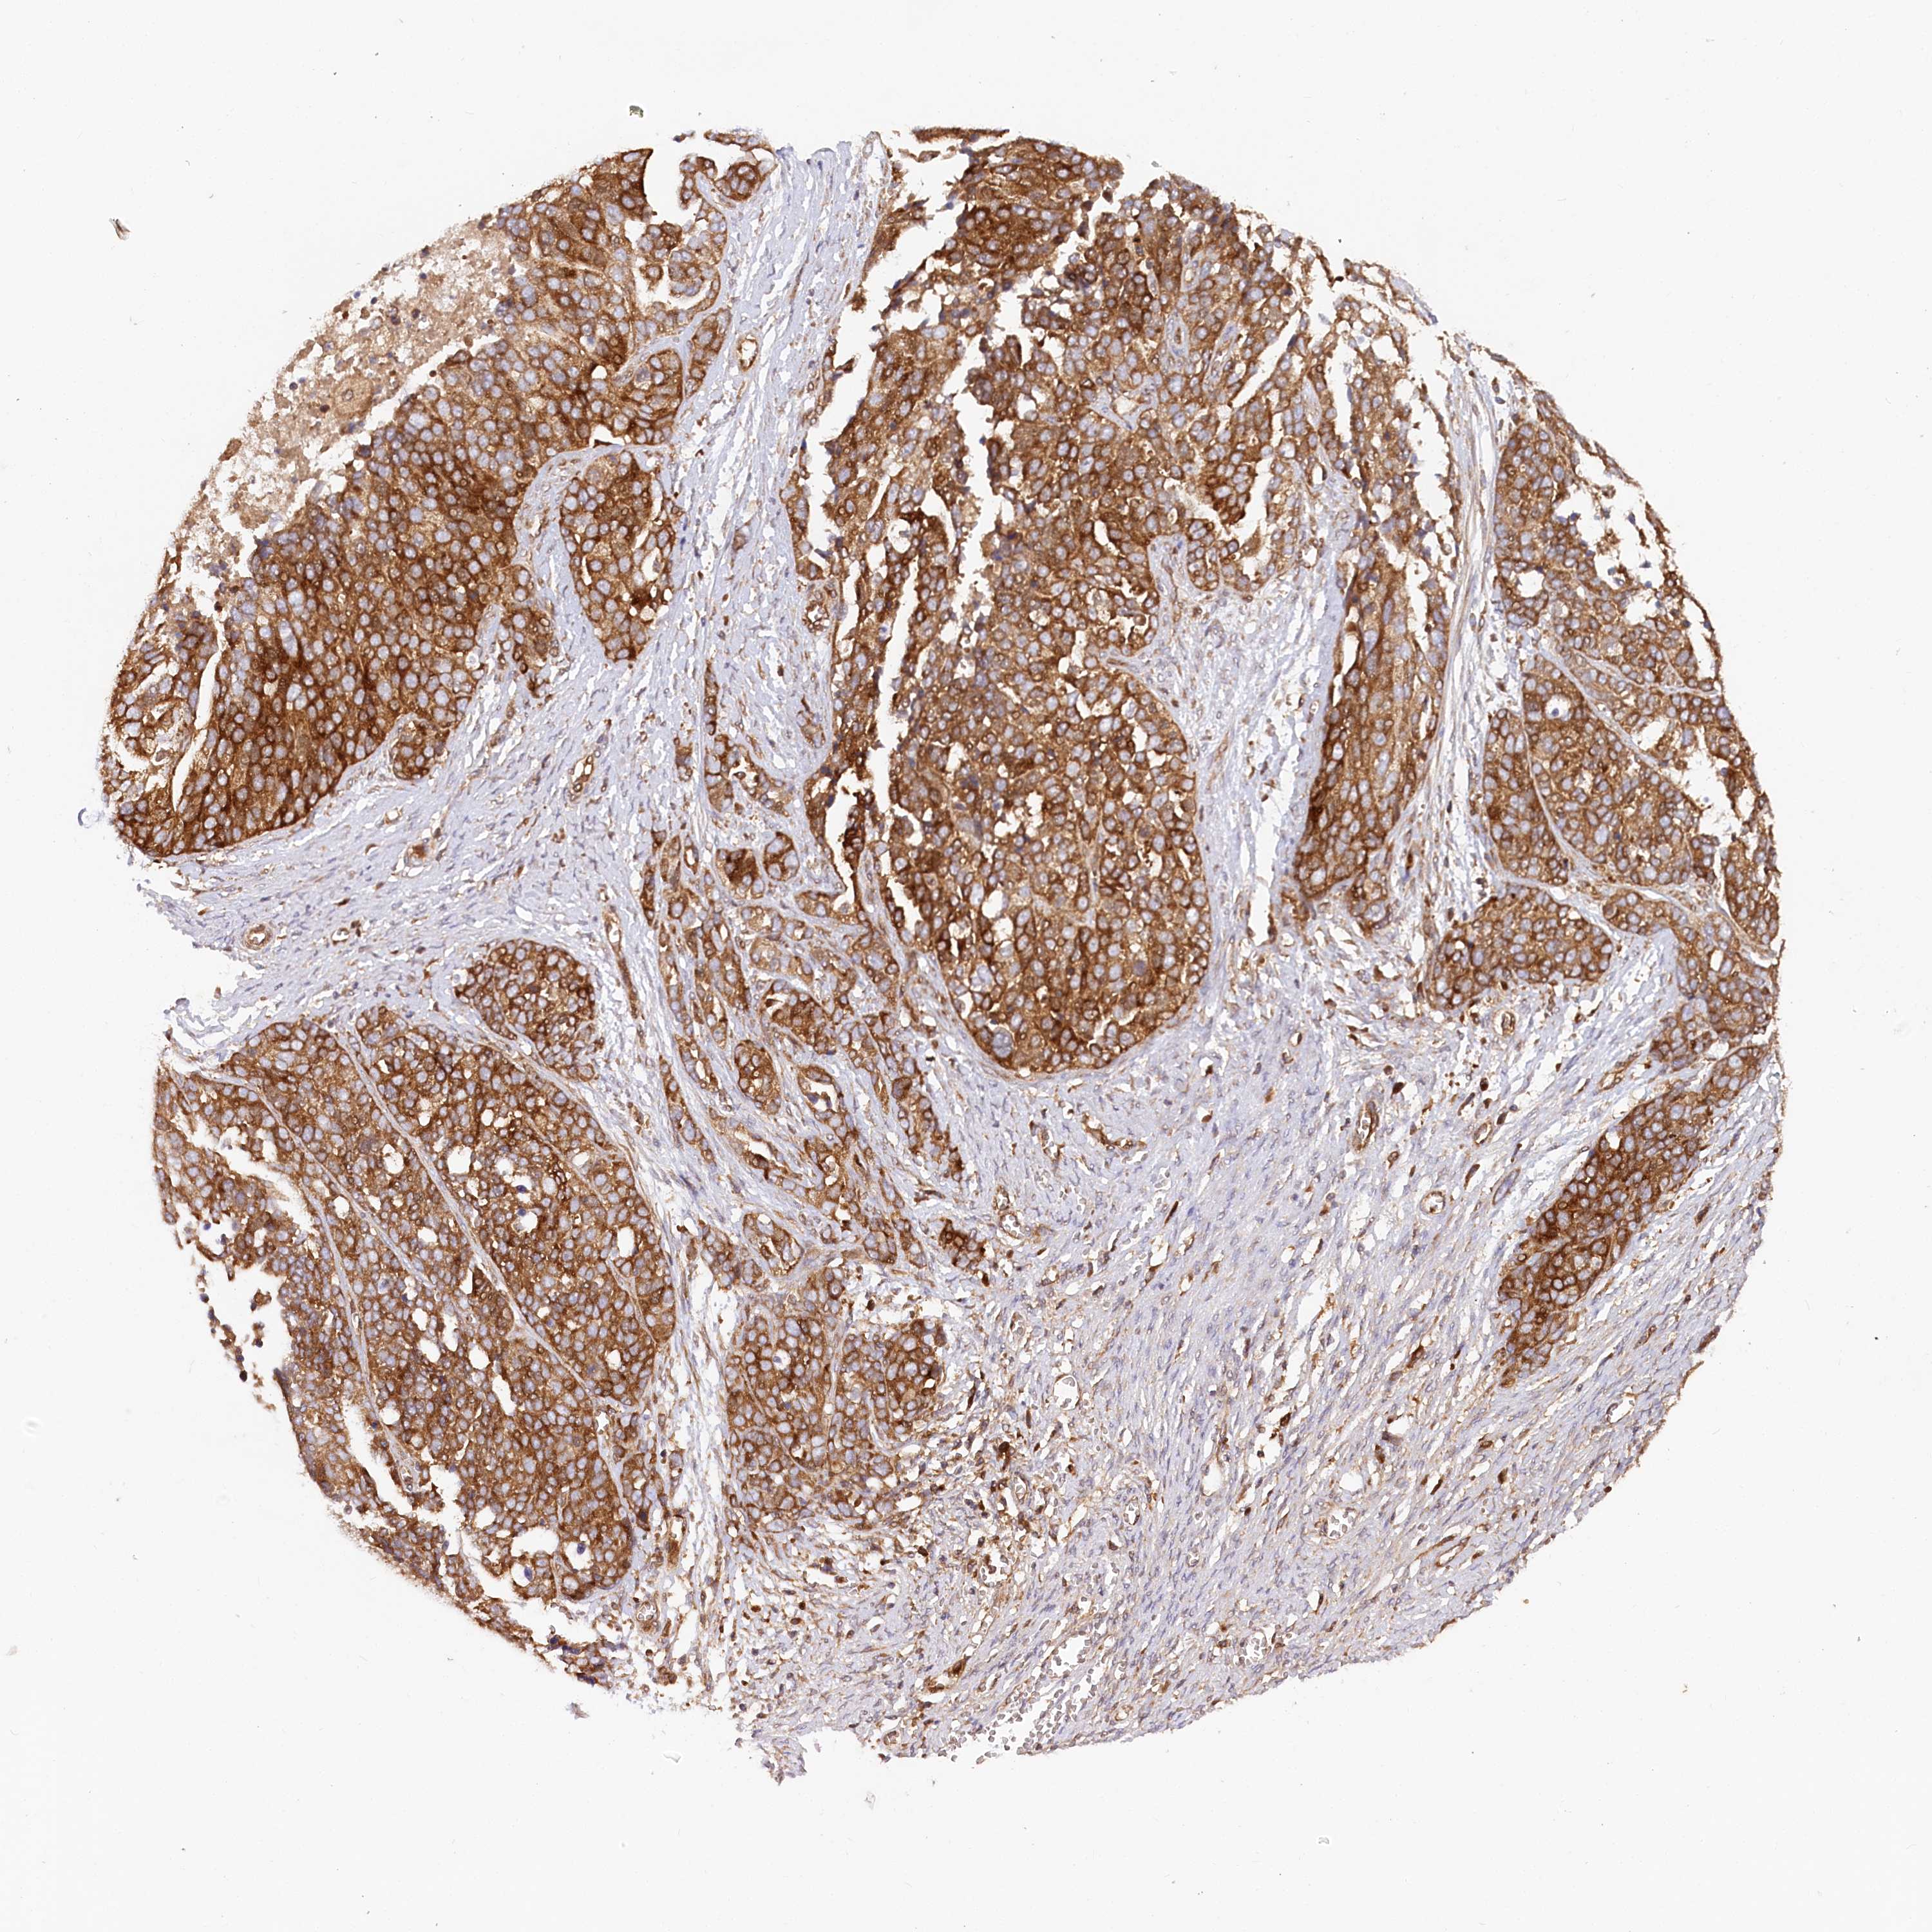

OVARIAN CANCER - Protein expressioni

A mouse-over function shows sample information and annotation data. Click on an image to view it in a full screen mode. Samples can be filtered based on level of antibody staining by selecting one or several of the following categories: high, medium, low and not detected. The assay and annotation is described here.

Note that samples used for immunohistochemistry by the Human Protein Atlas do not correspond to samples in the TCGA dataset.

Antibody stainingi

Antibody staining in the annotated cell types in the current human tissue is reported as not detected, low, medium, or high, based on conventional immunohistochemistry profiling in selected tissues. This score is based on the combination of the staining intensity and fraction of stained cells.

Each image is clickable and will lead to virtual microscopy that enables deeper exploration of all samples and also displays staining intensity scores, fraction scores and subcellular localization as well as patient and tissue information for each sample.

Antibody HPA035945

Antibody HPA056766

Antibody CAB037212

Staining

High

Medium

Low

Not detected

Cystadenocarcinoma, serous, NOS

Carcinoma, endometroid

Cystadenocarcinoma, mucinous, NOS

Carcinoma, NOS